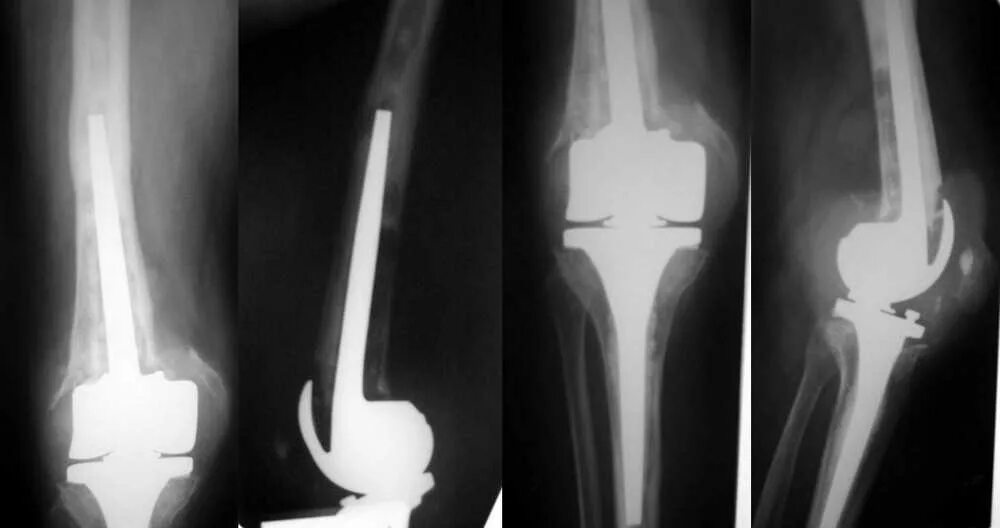

Эндопротез тазобедренного сустава мкб 10